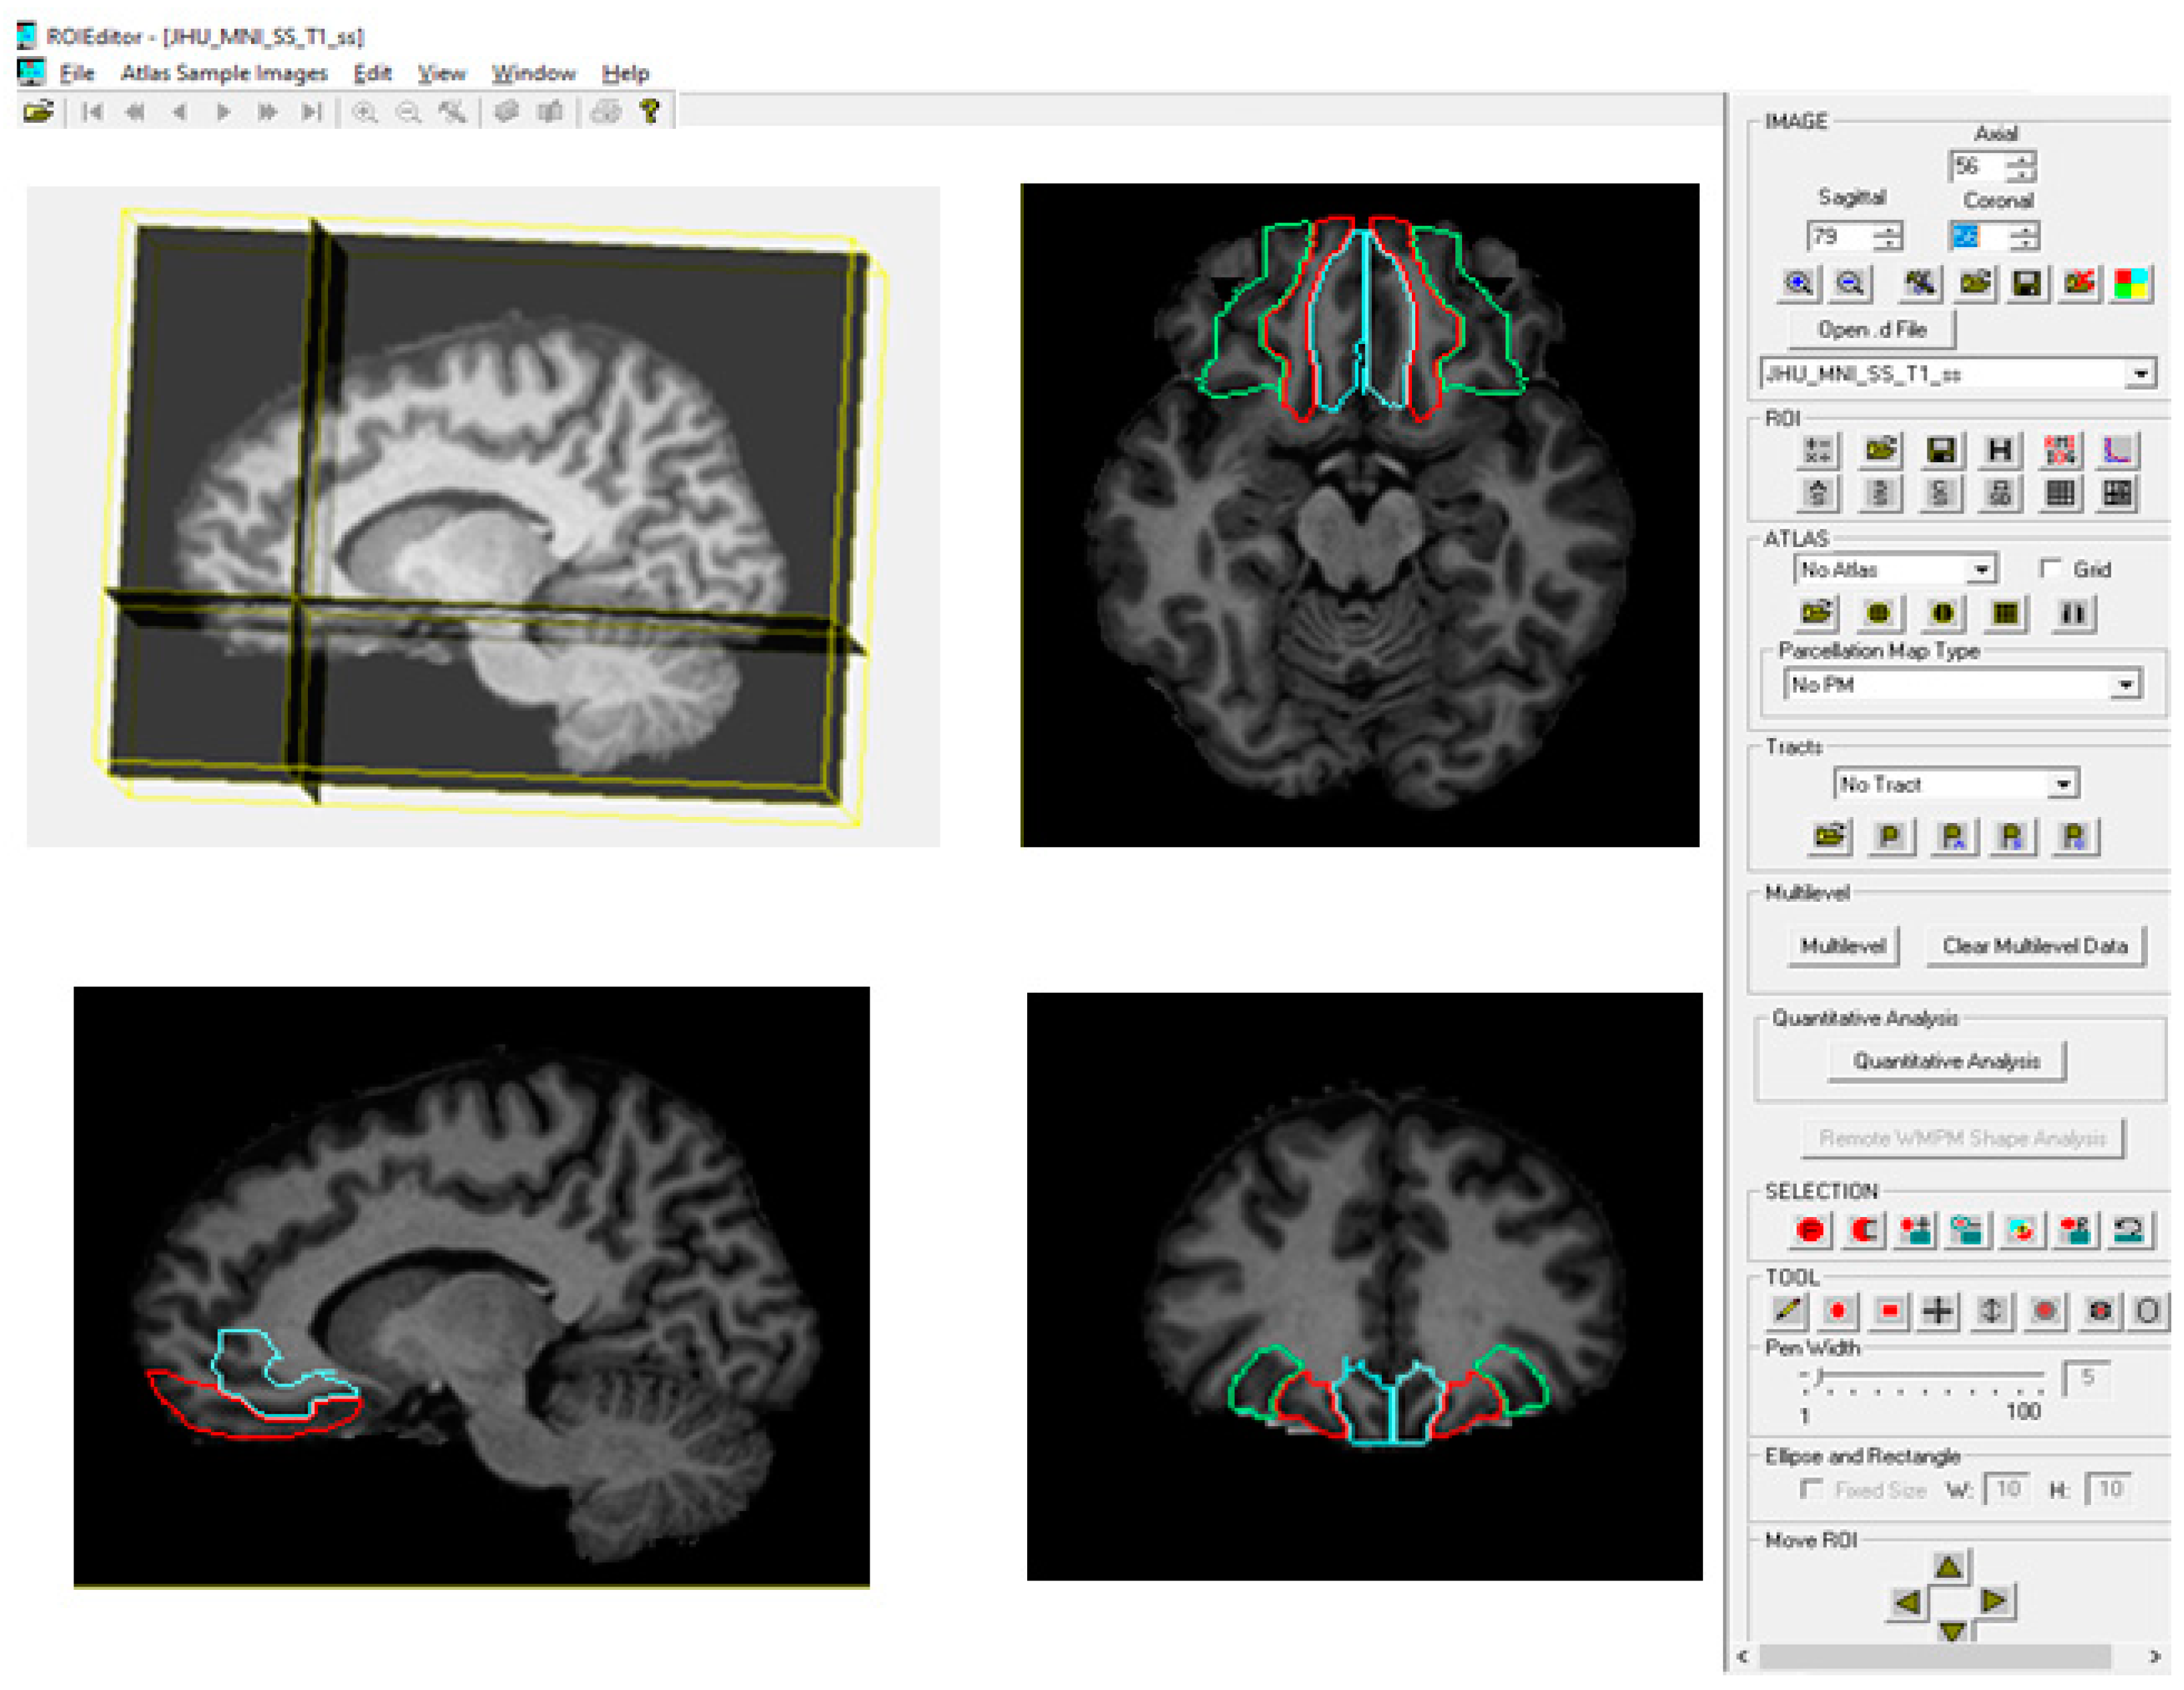

2.3.4. Automated Brain Parcellation (RoiEditor Processing)